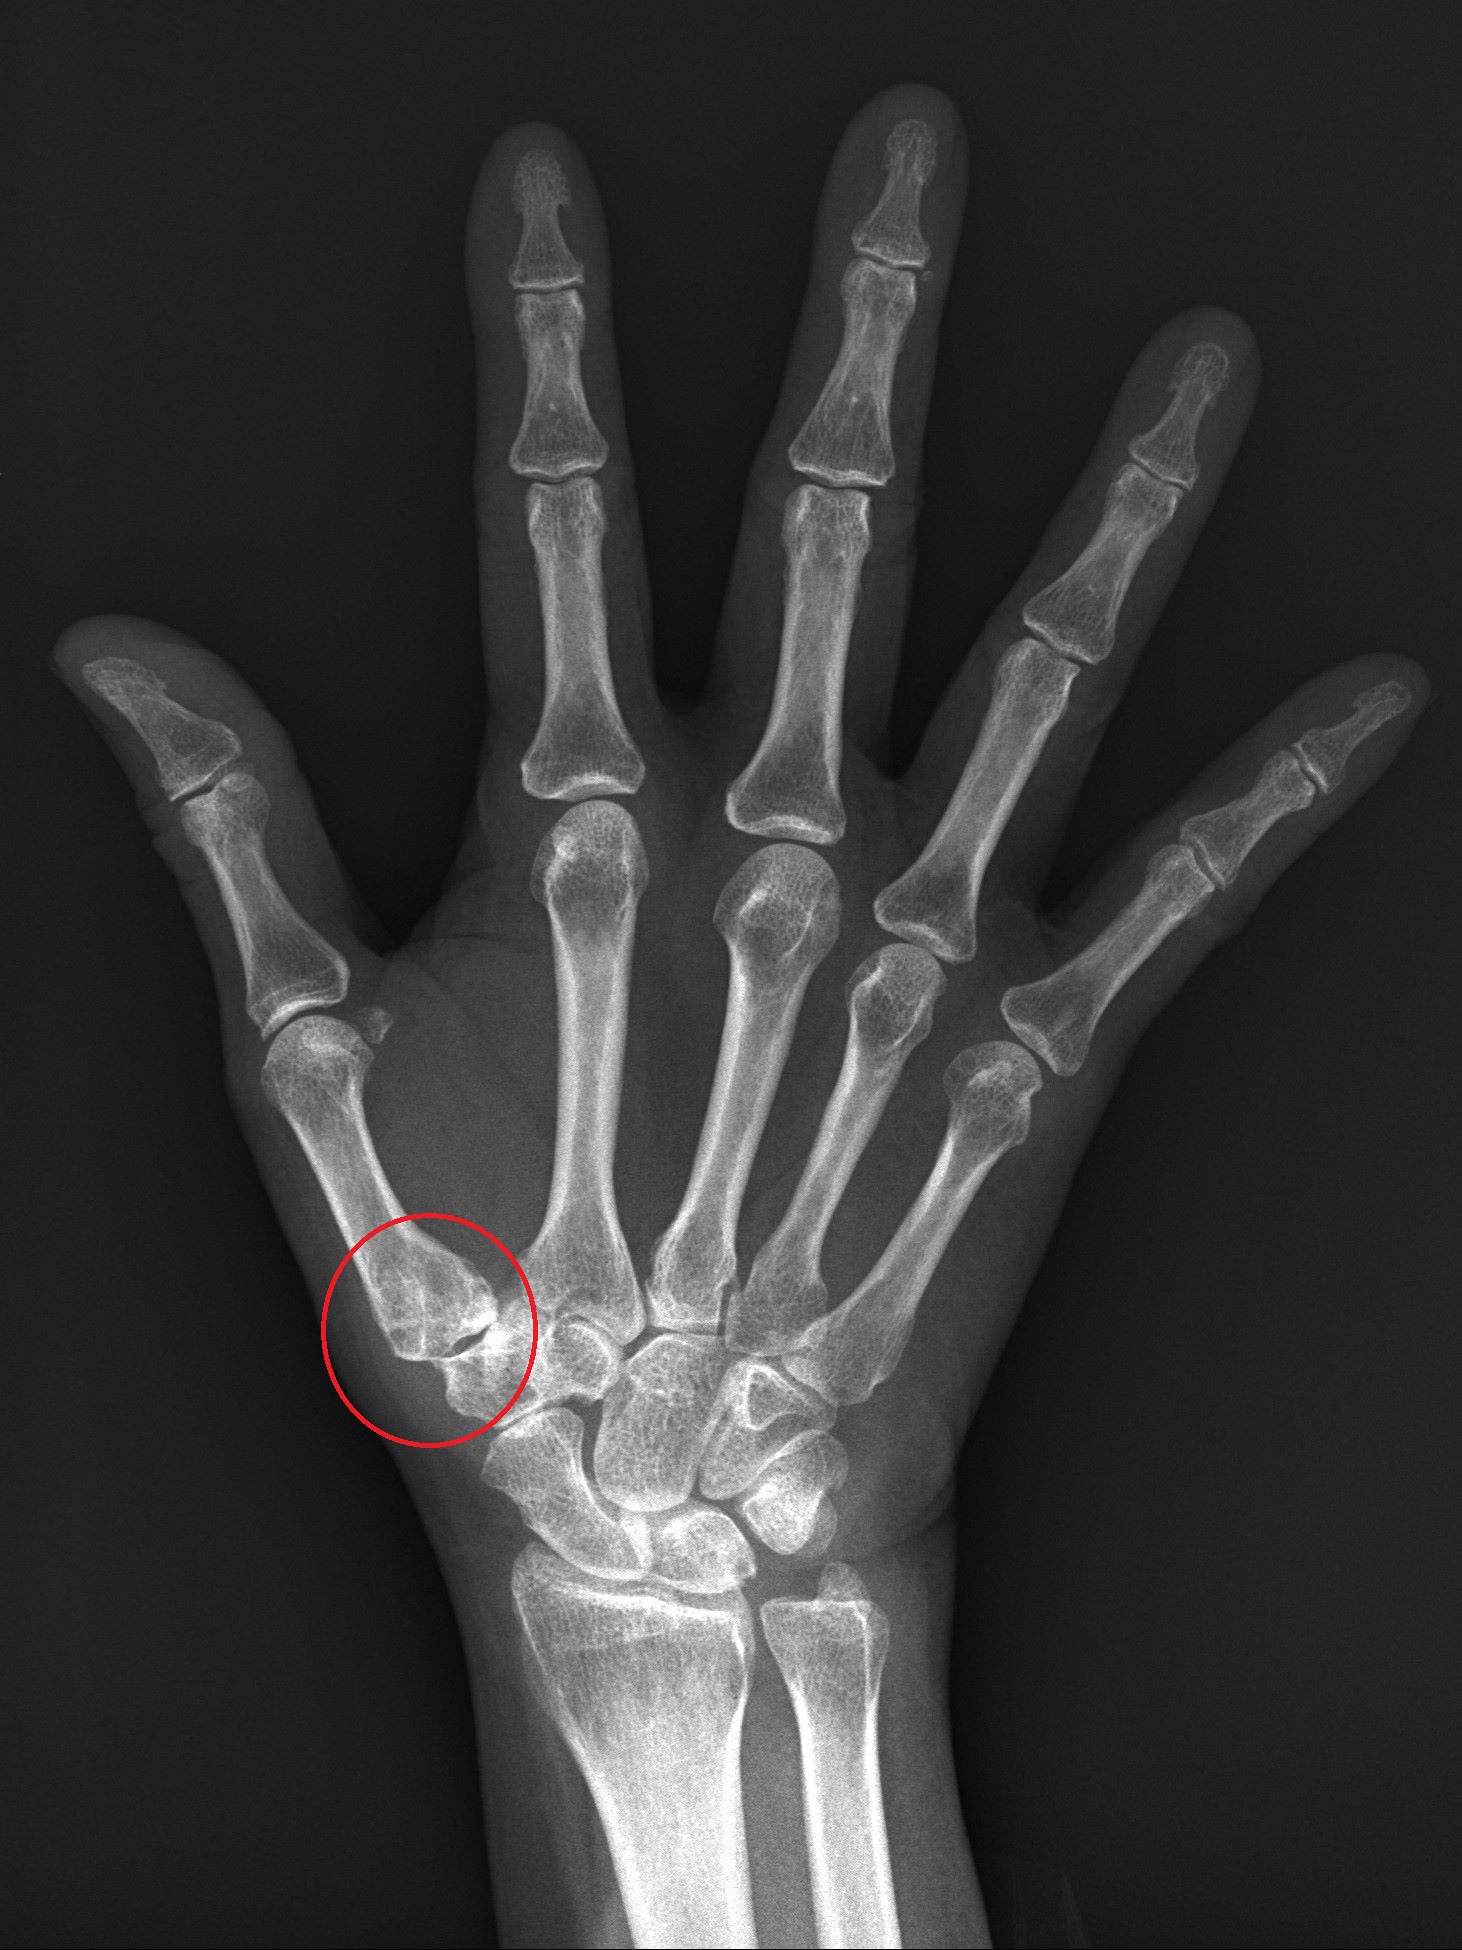

圖說 術前X光看到拇指根部關節有滑脫情形,微創手術會視情況用鈦合金或可吸收螺絲固定在第二掌骨基部

52歲的蔡女士從事美髮業,經常需要替人洗頭,但近來工作時經常覺得手腕疼痛,拇指無法出力,雖有去復健科就診,但止痛藥效果有限,因此到醫院骨科就診。X光發現,蔡女士的手腕因長期使用導致拇指腕掌關節磨損病變,導致她稍一施力關節就會脫離軸心。醫師以新式的微創手術將關節復位,不但不用住院,順利消除疼痛,也恢復工作機能。

臨床會以X光判斷關節磨損程度,若程度尚輕,可以用貼紮或護腕固定,加上止痛藥物控制,但在這樣的保守治療下仍然影響生活工作機能,就可採取手術。